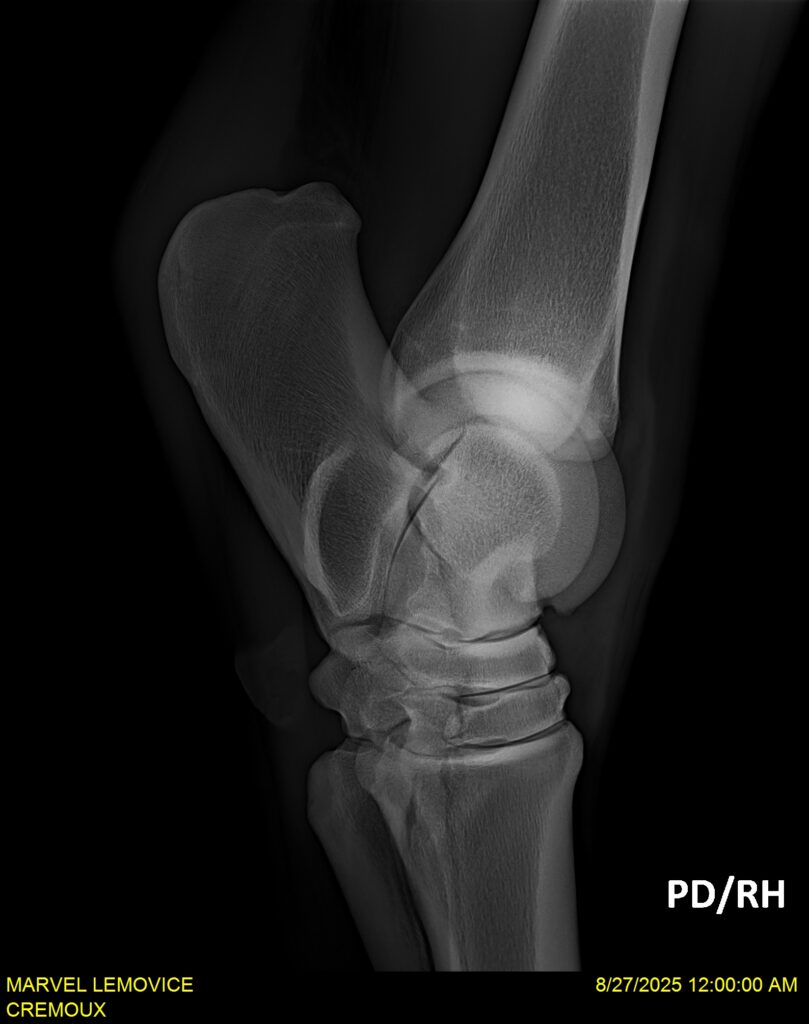

MARVEL LEMOVICE, hongre, Selle Français prend 4 ans en 2026. POPSTAR LOZONAIS x ROSIRE sur une excellente souche maternelle de l’élevage PLATIERE. Débourré aux trois allures et mise en route à l’obstacle. Super modèle avec du cadre et de la force, cheval respectueux avec des moyens. Très agréable au quotidien. Transport OK, maréchalerie OK, santé RAS, Bilan 20 clichés radios + clinique OK.

RADIOS ET CLINIQUE